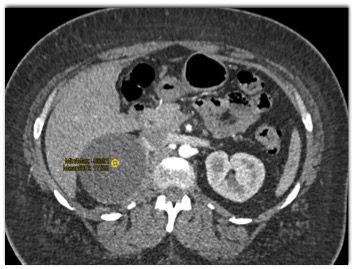

The most likely diagnosis in this case is?

cystic pheochromocytoma

adrenal cyst

adrenal adenoma

myelolipoma